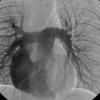

vessesls MR